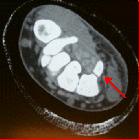

Sports-related

wrist and hand injuries: a review. Axial CT image demonstrating a hook of the hamate fracture (red arrow) in a college hockey player

nicht verwechseln mit: Os hamuli propriumHook of hamate fractures are rare. They occur from the hamate fracturing after blunt trauma, falls, and in sports player (e.g. golf, baseball, racquet sports) from a direct blow while swinging. Stress fractures have also been reported.

It may result in Guyon's canal syndrome.